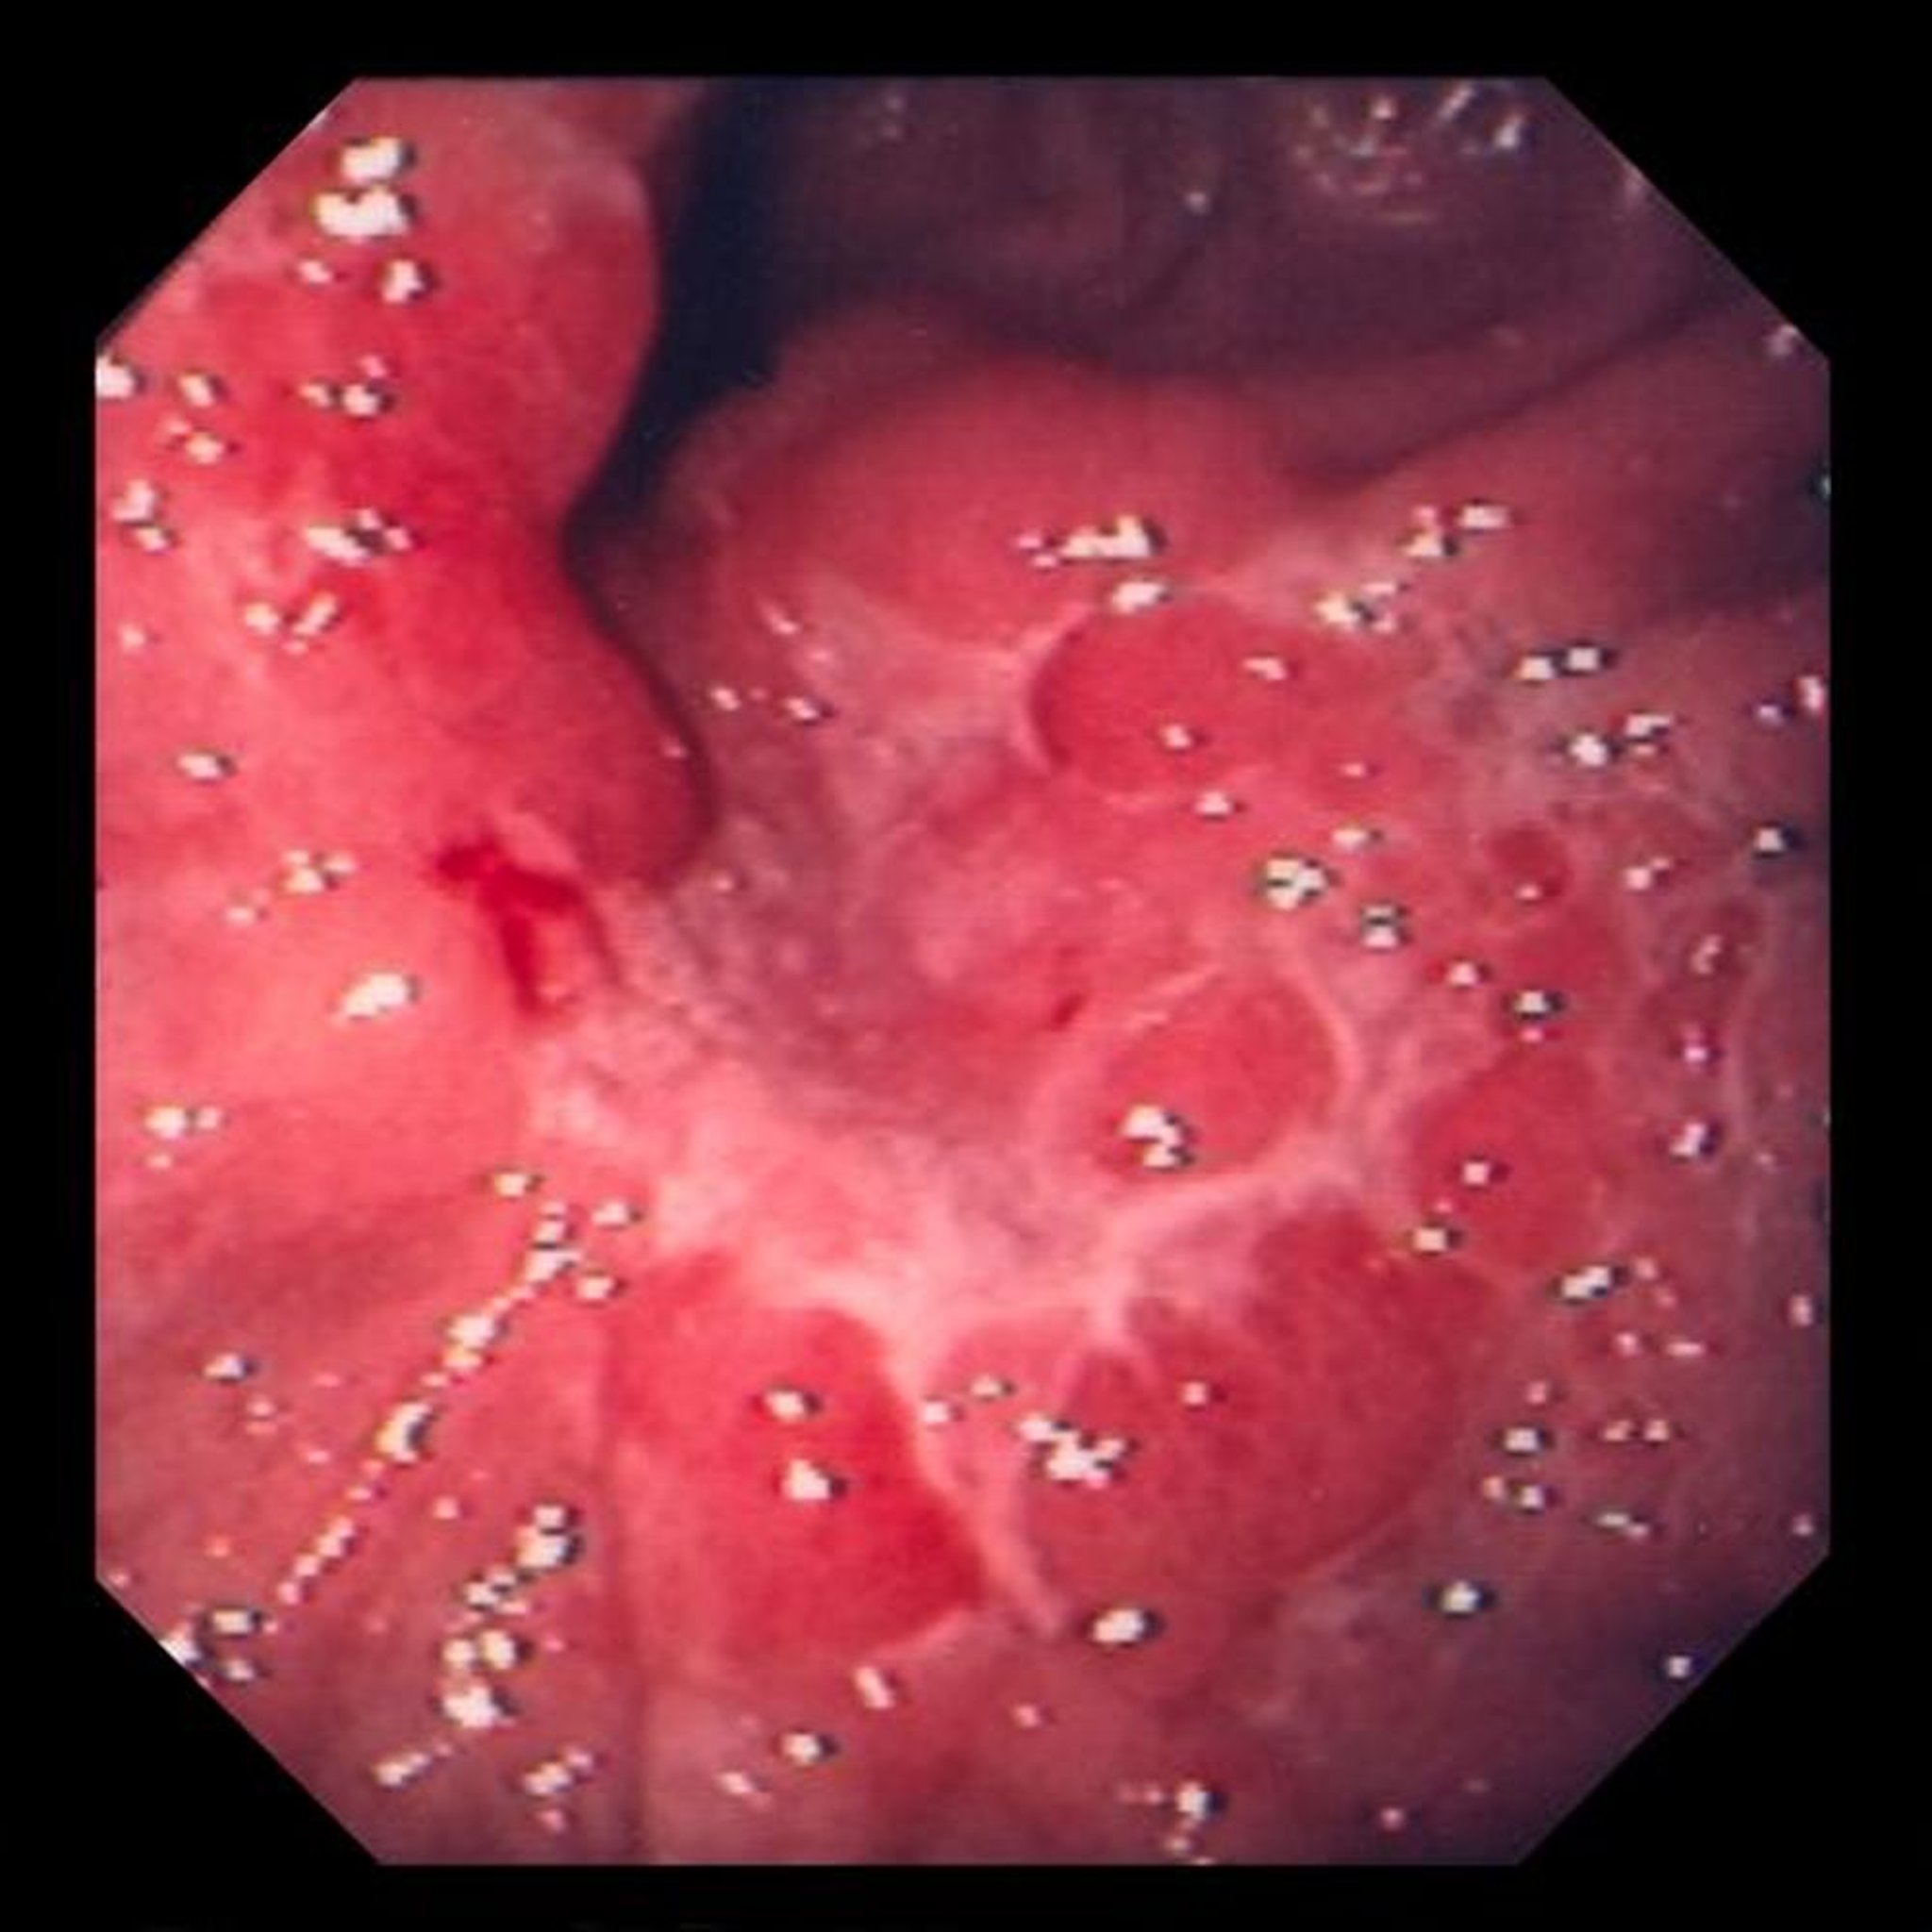

This image shows an ulcer within edematous mucosal folds, which, on biopsy, turned out to be poorly differentiated adenocarcinoma (signet ring cell type).

Image provided by David M. Martin, MD.